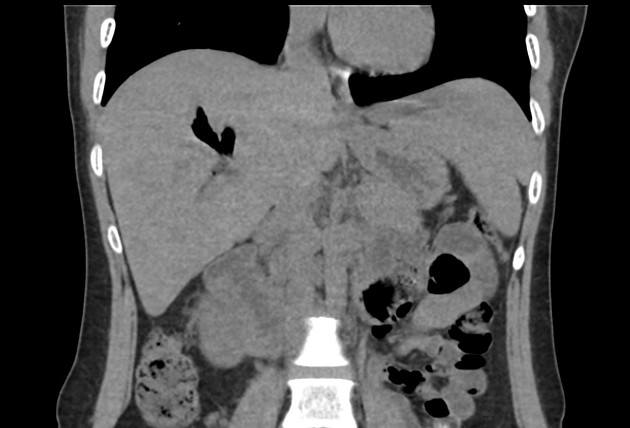

Khí đường mật

» Thông tin: Nữ giới – 30 tuổi.

» Lâm sàng: Đau mạn sườn phải / Tiền sử cắt túi mật.